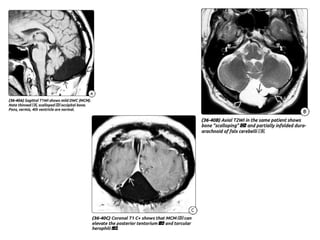

Other Imaging Findings:

โ€ข The straight sinus, sinus confluence, and tentorial apex are elevated above the lambdoid

suture ("lambdoid-torcular inversion").

โ€ข The transverse sinuses descend at a steep angle from the torcular herophili toward the

sigmoid sinuses.

โ€ข The occipital bone may appear scalloped, focally thinned, and remodeled with all

posterior fossa cysts.

โ€ข Retrocerebellar CSF cysts (formerly termed "mega cisterna magna") often

demonstrates partially infolded dura- arachnoid (falx cerebelli) on axial T2 scans.

โ€ข The falx cerebelli is usually absent in DWM.

Other Imaging Findings: โ€ขThe straight sinus, sinus confluence, and tentorial apex are elevated above the lambdoid suture ("lambdoid-torcular inversion"). โ€ข The transverse sinuses descend at a steep angle from the torcular herophili toward the sigmoid sinuses. โ€ข The occipital bone may appear scalloped, focally thinned, and remodeled with all posterior fossa cysts. โ€ข Retrocerebellar CSF cysts (formerly termed "mega cisterna magna") often demonstrates partially infolded dura- arachnoid (falx cerebelli) on axial T2 scans. โ€ข The falx cerebelli is usually absent in DWM. โ€ข Generalized obstructive hydrocephalus is present in over 80% of neonates with DWM at birth. โ€ข If callosal dysgenesis is present, the lateral ventricles are widely separated and may have unusually prominent occipital horns (colpocephaly).